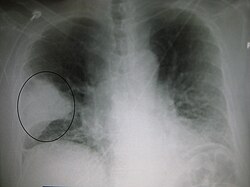

| 肺炎患者的胸腔X光照片,圈起處可看見明顯白色楔狀實變,此為細菌性肺炎的特点。 | |

由X光片來看,肺炎可以分類為大葉性肺炎、支氣管肺炎(有時也會稱為小葉性肺炎)及間質性肺病。細菌感染的社區性肺炎典型症狀有一個肺葉節段的肺實變,稱為大葉性肺炎。然而並非所有的細菌性肺炎皆為大葉性肺炎,也並非所有的大葉性肺炎皆由細菌所引起,其他肺炎也會有類似的情形。吸入性肺炎的特點是肺兩側底部及右肺葉呈現混濁。病毒性肺炎的X光片可能是正常的,也可能有過度充氣、兩側大片浸潤、或是類似細菌性肺炎的肺實變情形。肺炎在早期時可能無法從X光片上看出來,特別是在脫水的情況下,若有肥胖症其他肺部病史,也不易判斷。有些情形,X射线计算机断层成像可以看出一些進一步的資訊。